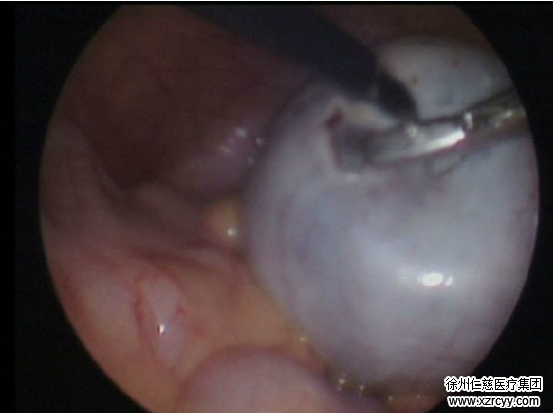

“通常卵巢畸胎瘤手术方式可选择腹腔镜或开腹。”鲍主任说,“开腹手术,伤口比较大,住院时间长。而betway在线登陆妇产科的腹腔镜技术,仅需在腹部开2个0.5-1cm的小口,伤口小,恢复快,术后并发症少。”7月23日,入院后第二天,在腹腔镜下张女士的卵巢畸胎瘤被确诊,并进行了手术。